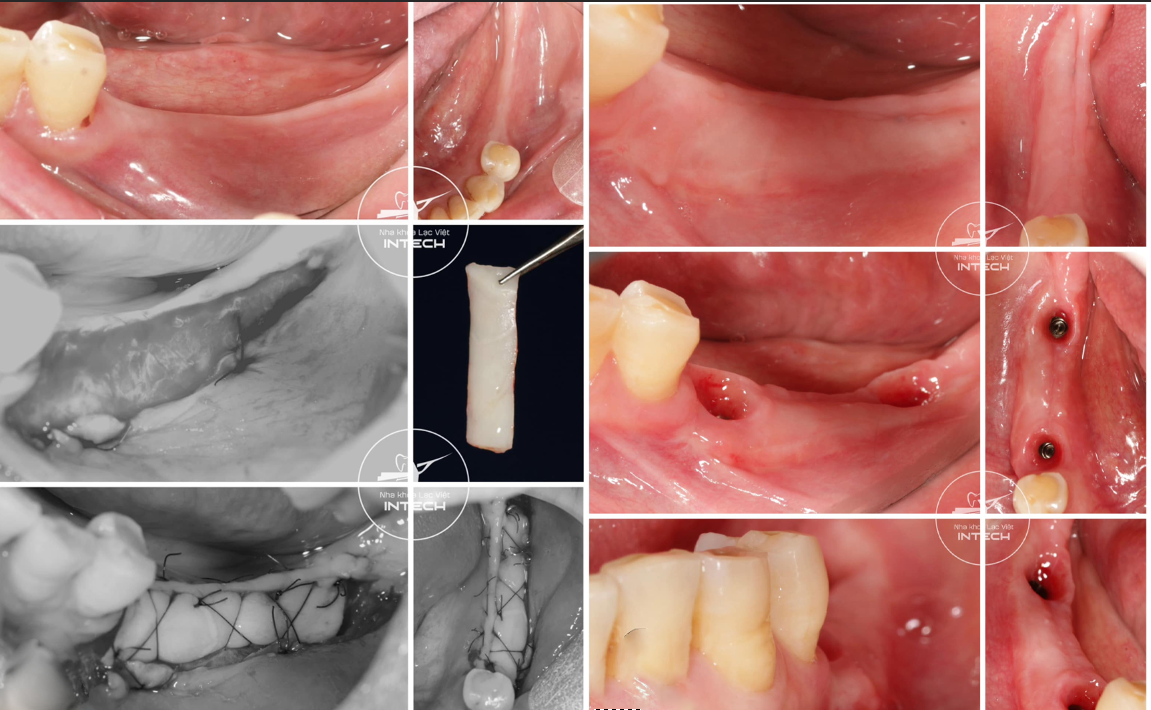

2.3. Sự ổn định của nướu răng xung quanh Implant

Khi trụ Implant được đặt đúng kỹ thuật, mô nướu sẽ ôm sát quanh cổ trụ, che phủ tốt và tránh tình trạng tụt nướu hoặc lộ trụ gây mất thẩm mỹ. Đối với vùng răng cửa hoặc trường hợp nướu quá mỏng, bác sĩ có thể chỉ định ghép nướu để cải thiện hình dáng và màu sắc viền nướu, tăng hiệu quả thẩm mỹ sau phục hình.

Bác sĩ tại nha khoa Lạc Việt Intech thực hiện ghép nướu an toàn, chính xác, ít xâm lấn, tái tạo viền nướu như răng thật

• Tái tạo thẩm mỹ hồng như răng thật: Quy trình DCT ứng dụng trụ lành thương và trụ phục hình cá nhân hóa để tái lập và giữ hình dạng mô nha chu, giúp vùng lợi uốn lượn mềm mại, ôm sát răng sứ như răng thật, mang đến hiệu ứng thẩm mỹ hồng tự nhiên mà phương pháp truyền thống khó đạt được.